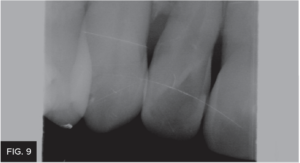

Photographs were taken to evaluate aesthetic outcome. The patient was shown her new restoration and was pleased with the results. The patient returned a few weeks later for a final post-op check. The tissue healed well after removal of the attachments. Proper canine function was confirmed and lateral disclusion of the lateral was obtained which is ideal with a Class IV restoration on such a small sized tooth.12 The final pictures2 and post-op x-rays were taken. (FIG 8 & 9)